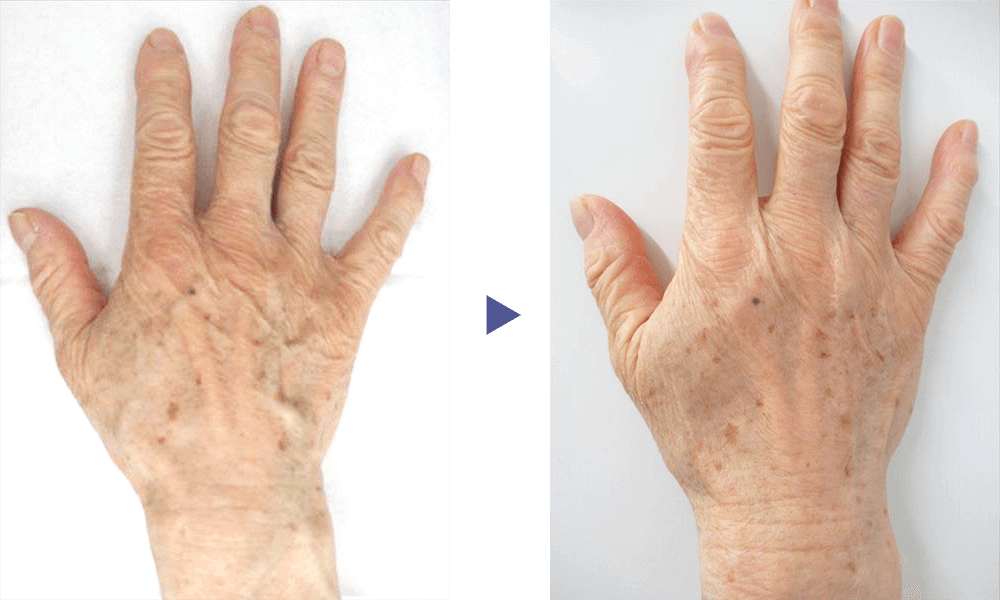

手の甲の血管や、前腕の血管などがボコボコと浮き出る症状を治療します。

硬化療法や血管内レーザーで治療することで、血管を目立たなくする効果が見込めます。

「手(hand)」と「静脈(vein)」を合わせて、「hand vein(ハンドベイン)」と呼びます。 発症すると、手の甲や前腕部の血管が数ミリ〜5ミリ程度に拡張し、こぶのように膨れて目立つため、見映えに影響が出ます。特に、手の甲は日常的に人目につく部位なので、血管が過剰に浮き出ていることを気にして悩んでいる患者様は多くいらっしゃいます。

ハンドベイン自体は病気ではなく、放置していても何らかの健康被害が出るわけではないのですが、加齢による老化と共に症状が進行する特徴があり、10代〜20代では目立たなかったはずの血管が目立つようになり、若々しさを欠いた、年老いた印象の手・前腕になってしまうのです。

ハンドベインの治療は、メスを用いた大掛かりな手術などを行う必要がないため、術後の生活に大きな制限が出るようなことはありません。 また、硬化療法や血管内レーザー治療を行った血管が、再び膨れてくるというケースはほとんどないです。 ただし、治療した静脈血管以外の部分が目立ってくる場合がありますので、その際には新たに治療が必要となります。